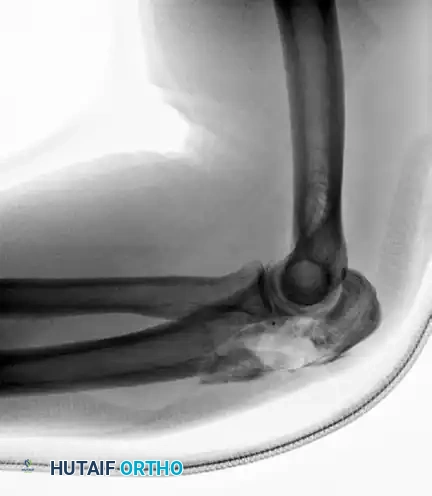

Complex Fracture-Dislocation of the Elbow (Pre-op AP):

Complex Fracture-Dislocation of the Elbow (Pre-op Lateral):

Fixation with Multiplanar Locking Intramedullary Nail (Post-op AP):

Fixation with Multiplanar Locking Intramedullary Nail (Post-op Lateral):

INTRAMEDULLARY NAILING FOR PROXIMAL ULNA FRACTURES

Recently, there has been a resurgence of interest in the use of intramedullary (IM) nails for the treatment of proximal ulna and olecranon fractures. The biomechanical advantage of IM nailing lies in its load-sharing capacity and minimal soft tissue disruption, which is highly advantageous in patients with compromised posterior skin envelopes.

More advanced, dedicated implants have since been developed. Nijs et al. reported excellent outcomes using an olecranon osteotomy nail (OleON, Synthes). Furthermore, Edwards et al. demonstrated the efficacy of a multiplanar locking intramedullary nail (OlecraNail, Mylad Orthopaedic Solutions) for the treatment of proximal olecranon fractures, including those presenting with complex, multi-directional instability patterns.